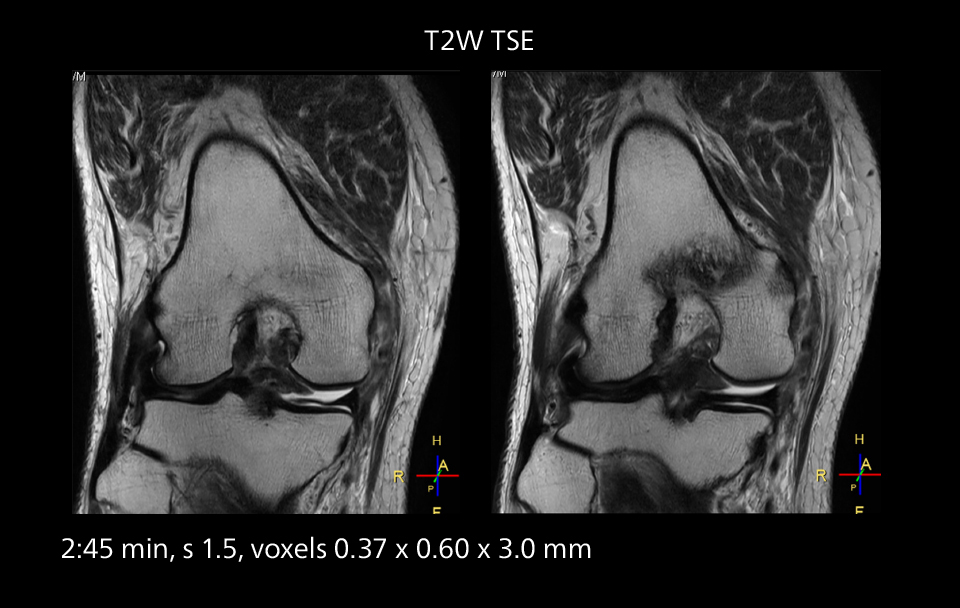

Diffusion studies benefit from powerful gradients

The high performance of the Vega HP gradients is particularly impressive in DWI. “The Vega HP gradients enable us to scan faster and use b-values as high as 2000, for example in prostate DWI and in DWIBS, which provides image quality that is remarkably improved over the previous system and we are able to more easily see lesions.”

MRI of prostate

Examples of prostate imaging showing faster scan times and improved resolution illustrate the power of SmartPath to Elition X in this case of prostate cancer with PI-RADS score 4.